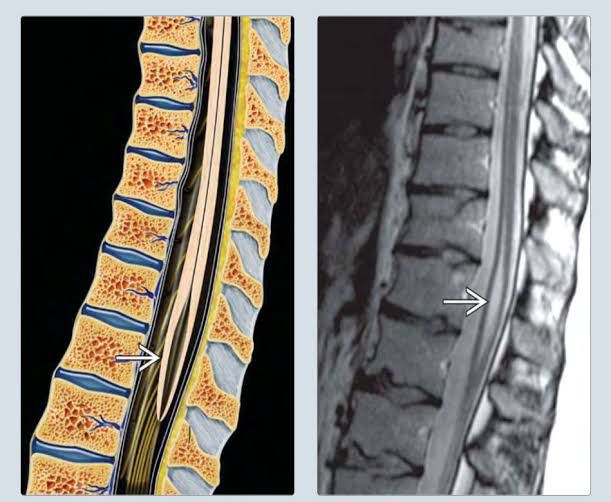

The terminal ventricle (ventriculus terminalis) - sometimes also known as 5th ventricle - is widest part of the central canal of the spinal cord, lined by ependyma, that is located at or near the conus medullaris. The central canal expands as a fusiform terminal ventricle, and is approximately 8–10 mm in length in the conus medullaris (or conus terminalis). Although the terminal ventricle is visible in the fetus and children, but is usually absent in adults. In some rare cases, it can persist in adults, where it can be an occasional finding on radiological investigations or it can display insidious and non-specific symptoms due to progressive cerebrospinal fluid (CSF) accumulation and cystic enlargement of the cavity. Symptoms may vary from aspecific signs to sphincter dysfunctions and focal neurological deficits. The correct management of this condition is still an object of debate due to its rarity and its unpredictable behaviour in adult patients. Only those patients with neurological deficits clearly related to the terminal ventricle could benefit from surgery.